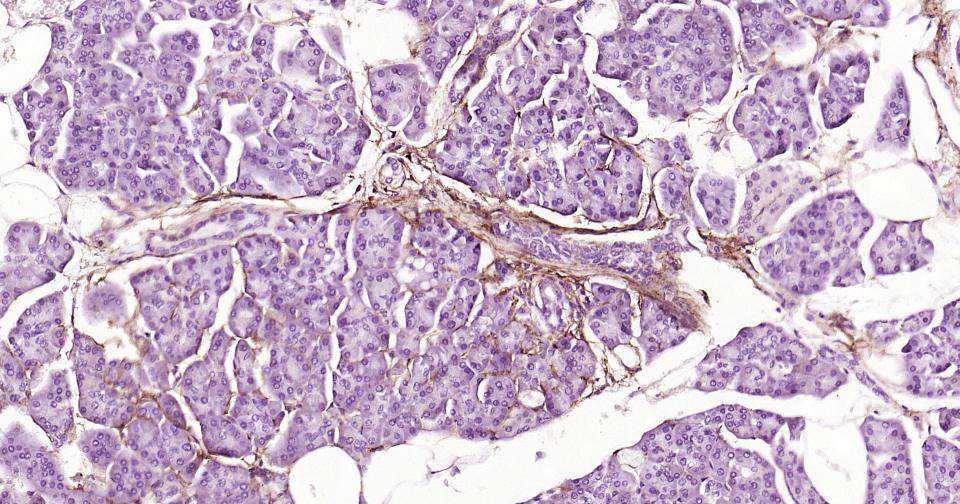

Paraformaldehyde-fixed, paraffin embedded Human Pancreas; Antigen retrieval by boiling in sodium citrate buffer (pH6.0) for 15 min; Antibody incubation with NGFR/p75NTR Monoclonal Antibody, Unconjugated(bsm-52253R) at 1:200 overnight at 4°C, followed by conjugation to the bs-0295G-HRP and DAB (C-0010) staining.